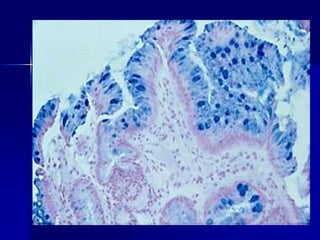

Una mujer de 43 años con

antecedentes de 5 años de náuseas

intermitentes, vómitos, y dolor

epigástrico tiene un examen

endoscópico que revela gástrico

eritema y erosiones. El aspecto

microscópico de una muestra de

biopsia es mostrado.

1. ¿Cuál es su diagnóstico?

2. ¿Qué citocinas aumentan?

3. ¿Qué genes microbianos

contribuyen a la patogenia?

4. ¿Están estos organismos presentes

en el duodeno?

A. Hay un infiltrado linfoplasmocítico denso superficial en la lámina propia. B. Agregado linfoide; cuando está presente,

es altamente sugestivo de Helicobacter. C. Los neutrófilos se encuentran dispersos en el infiltrado de la lámina propia y

pueden penetrar el epitelio glandular. D. La tinción de Warthin- Starry resalta los pequeños organismos curvilíneos en la

superficie foveolar